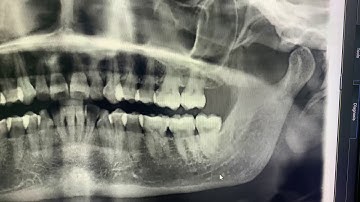

Distoangular Tooth Extraction